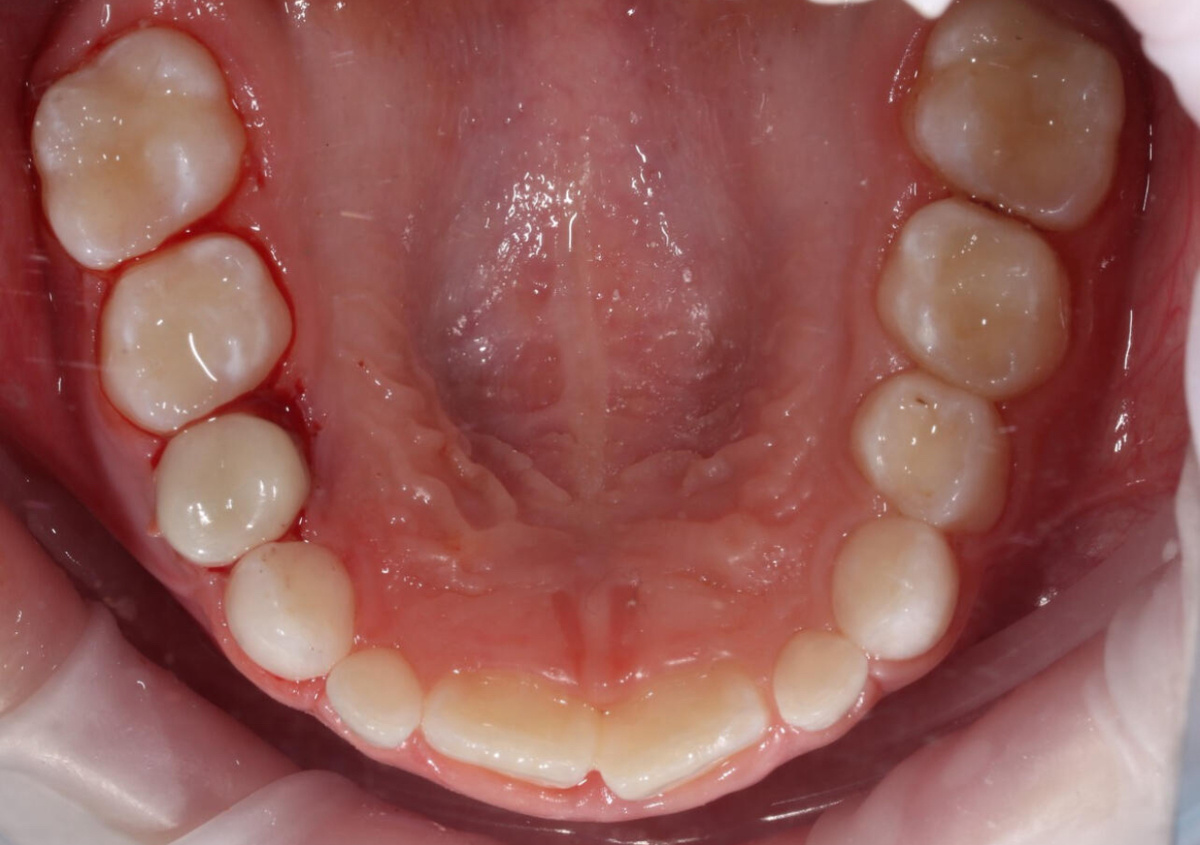

ДО ЛЕЧЕНИЯ

ПОСЛЕ ЛЕЧЕНИЯ